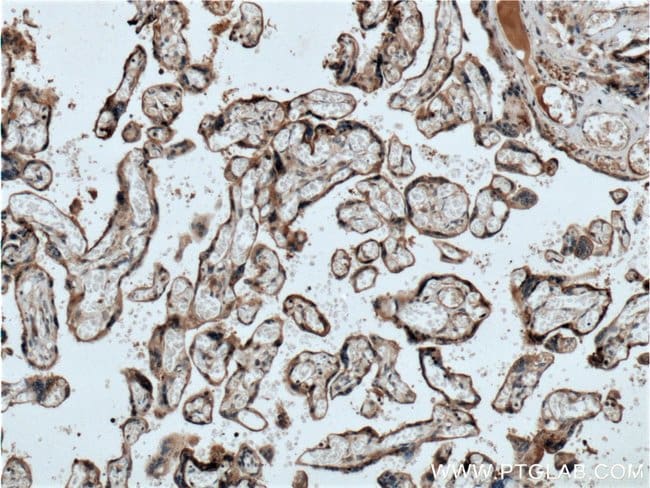

GPSM2 Rabbit anti-Human, Mouse, Rat, Polyclonal, Proteintech

Immunocytochemistry, Immunofluorescence, Immunohistochemistry (Paraffin), Western Blot | |

GPSM2 Fusion Protein Ag25195 | |

Human, Mouse, Rat | |